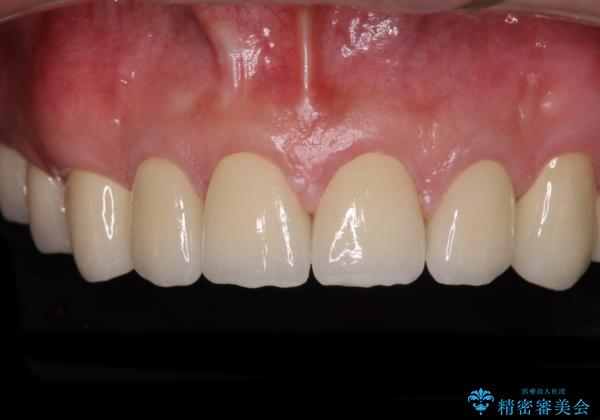

当初は前歯6歯をオールセラミッククラウンで補綴する予定でしたが、前歯が綺麗に仕上がったことで、奥歯まで延長して補綴することとしました。

黄ばんだ前歯や白すぎたクラウン、プラスチックの継ぎ接ぎなどを全てオールセラミッククラウンの統一感のある前歯に仕上げました。